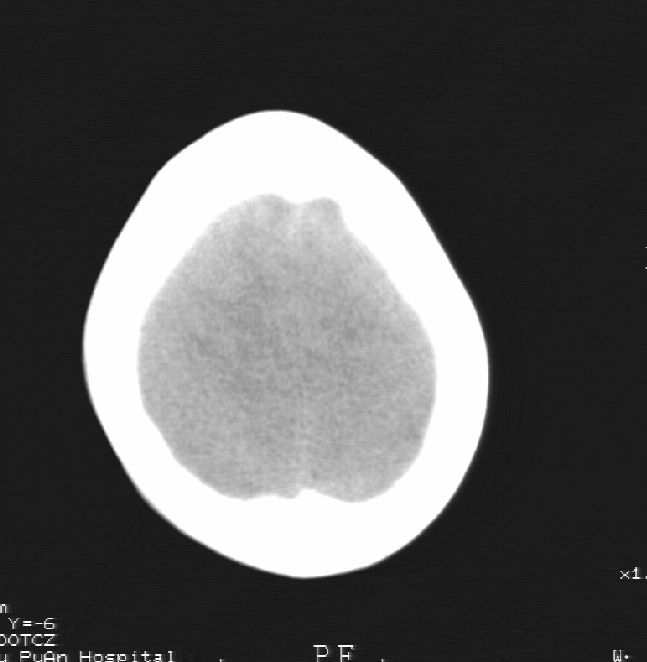

患者男,22岁,因外伤入院,低密度影ct值约-120hu。